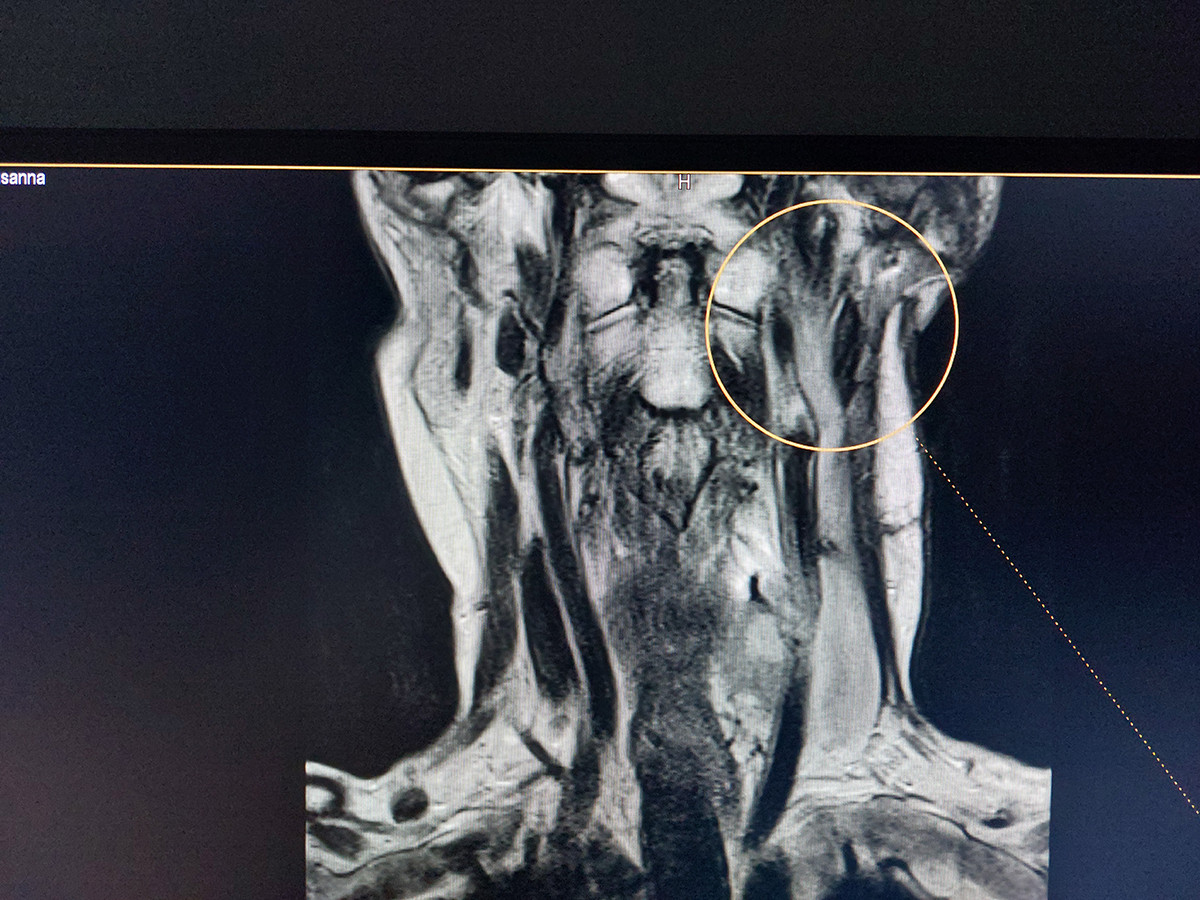

Նախքան «Նաիրի» ԲԿ դիմելը պացիենտի մոտ ախտորոշվել է հարականջային թքագեղձի ադենոմա։ «Նաիրի» բժշկական կենտրոնում կատարվել է թքագեղձի մագնիսա-ռեզոնանսային տոմոգրաֆիա, և պարզվել, որ ավելի քան 5 տարի գոյություն ունեցող թքագեղձի ադենոմայի ներսում առկա է մոտավորապես 1 սմ պինդ գոյացություն։ Իրականացվել է հայտնաբերված պինդ գոյացության պունկցիոն բիոպսիա և, արդյունքում, ախտորոշվել է ուռուցք` թքագեղձի ադենոկարցինոմա: Սա այն դասական դեպքերից է, թե ինչպես կարող է բարորակ գոյացությունը, տարիներ շարունակ անտեսելու, չբուժելու արդյունքում վերաճել չարորակ ուռուցքի։

Քանի որ գոյացությունը մեծ էր և շատ մոտ էր գտնվում դիմային նյարդին (դիմային նյարդը նյարդավորում է դեմքի միմիկայի բոլոր մկանները), կատարվեց ամբողջական հեռացում: Մանրադիտակի կիրառման պայմաններում դիմային նյարդն ամբողջապես պահպանվեց։ Երկու-երեք ամիսների ընթացքում դեմքի միմիկայի բոլոր մկանները վերականգնվեցին՝ թե՛ ֆունկցիոնալ, թե՛ էսթետիկ առումով, ինչը թույլ տվեց մեր պացիենտին շարունակել իր մասնագիտական գործունեությունը։